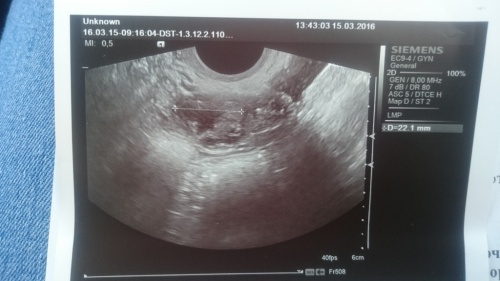

Нашли ЖТ - 20,4 на 22,1 мм, эндик - 8 мм.

Но УЗИстка была не в настроении явно и сказала, что ничего хорошего не видит и ЖТ у меня хиленькое, и кровоток плохой, явно гормонов каких то не хватает. Сказала, что ЖТ наверное давно, по этому такое (хотя О точно на 20 дц - не раньше), и дальше пойдет только на убыль(((